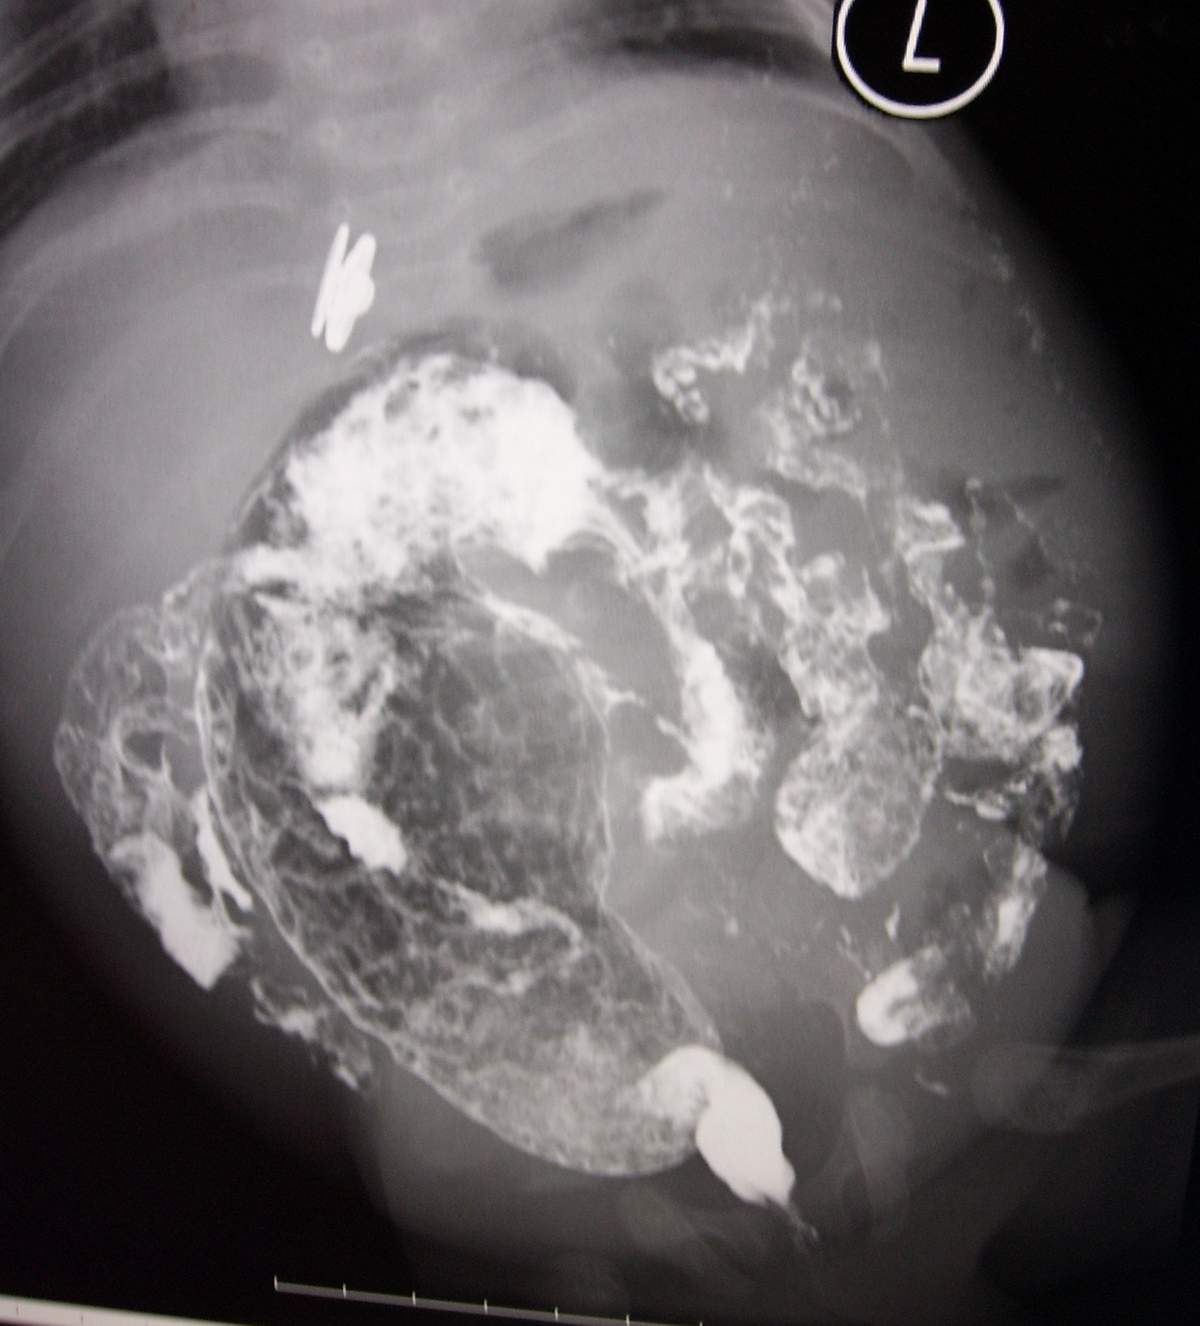

标题: PED0054:[讨论][分享]小儿钡灌肠!

男,2月,腹胀2天。

巨结肠

巨结肠很典型

大家说得都太粗了吧,诊断巨结肠总的说明那一段有问题吧。这样治疗起来才有方向。

我觉得是直肛型的巨结肠,可以先扩扩肛试一下。